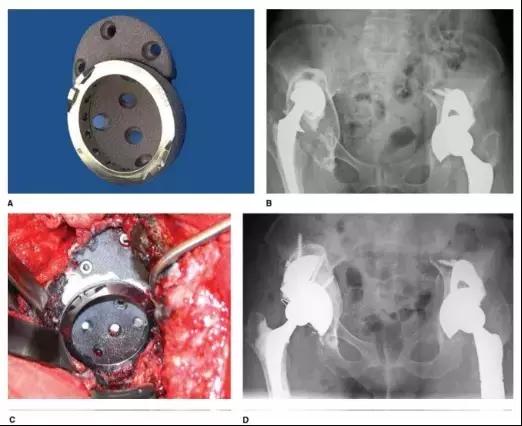

近年来钽金属块问世,其有更好的骨长入面积和抗剪切界面强度,而且较高的摩擦系数可以保证初始稳定,这些对臼杯获得远期生物固定非常关键。联合结构性植骨或金属骨小梁垫块可解决 Paprosky III A 及大部分 III B 型骨缺损,中远期随访结果良好(图 3、4)。

图 3 (A)多孔钽金属垫块置于非骨水泥髋臼假体上方 (B)术前 X 线提示右 IIIA 型髋臼骨缺损 (C)术中非骨水泥髋臼假体联合多孔金属加强块 (D)右髋翻修术后 X 线